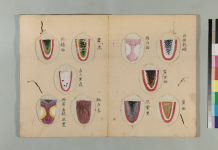

先日撮影した

写真を添えます。